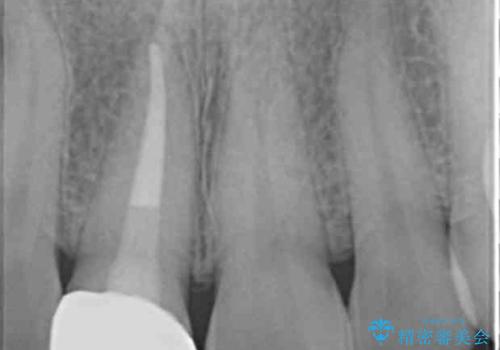

- 歯ぐきに、にきびのようなものができ治らない、と治療を希望され来院されました。

歯髄の検査、X線検査より神経の失活が確認されたので、根管治療・ファイバーコア築盛 ・ジルコニアクラウンの製作、と治療を進めます。

根管治療を行ったことで、歯ぐきのできものは治癒し再発をしなくなりました。